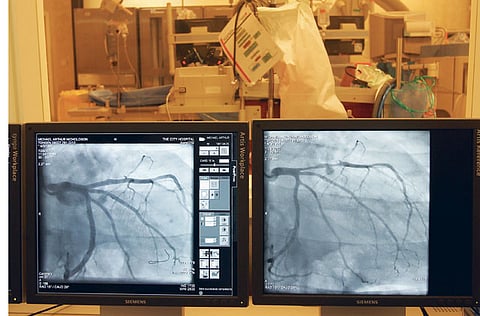

Coronary angiogram

If a doctor suspects that there is a narrowing or blockage in the arteries that supply the heart muscles with blood, he will perform a coronary angiogram.

The procedure is done in a hospital and uses X-ray imaging to examine the heart. The patient will be awake during the procedure. However, the area (usually the groin) where the catheter (a long, thin, flexible plastic tube) is inserted will be numbed.

The catheter is inserted into the artery and threaded to the heart or coronary arteries. A dye or contrast is injected through the catheter into the arteries and blood vessels while several X-ray images are taken.

If there is a narrowing or blockage the cardiologist will perform an angioplasty to widen the blood vessel.